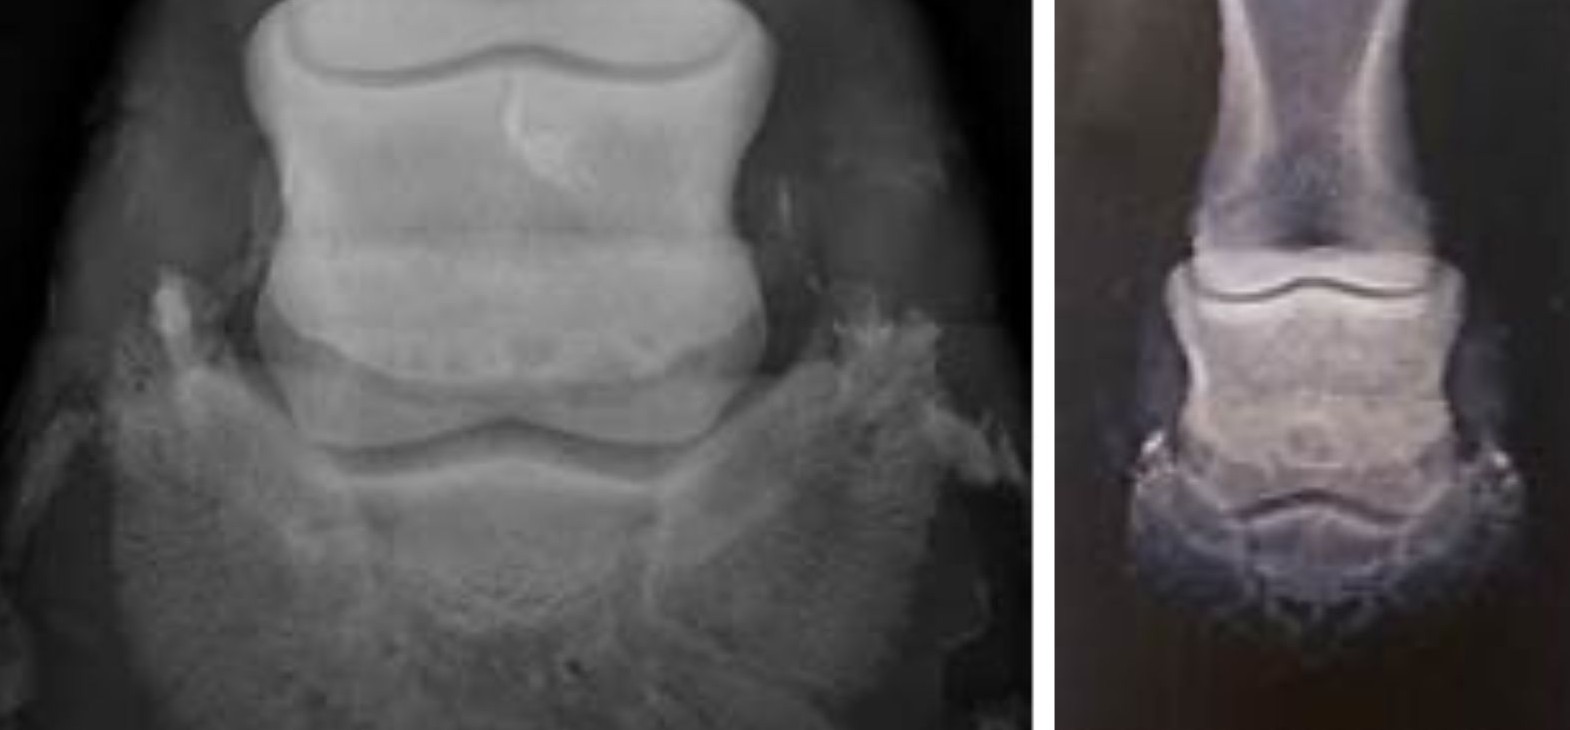

Il existe plusieurs tests afin de poser un diagnostic. Seuls les vétérinaires sont habilités à le faire. Il y a la pince à sonder sur la zone du naviculaire, le test de flexion, le test de la planche , et enfin la radio en vue skyline permettant de mettre en évidence la surface osseuse de l’os naviculaire.

C’est en général le stade qui suit le syndrome naviculaire si rien n’est fait. Le cheval est boiteux, et positif à l’ensemble des tests. Il présente des lésions osseuses lors des radios de contrôle. On observe alors l’élargissement des foramens. Cet état inflammatoire peut atteindre l’os, mais aussi provoquer une inflammation et une atteinte de la bourse naviculaire qui permet de lubrifier le passage du tendon fléchisseur profond sur l’os (bursite). On peut aussi observer une inflammation ou des lésions sur le TFP. Dans certains cas extrêmes, l’os peut aussi présenter un kyste (trou) important. Les atteintes osseuses ne sont malheureusement pas rattrapables. La douleur peut quant à elle, être diminuée voir complètement gérée. Le pronostic sportif du cheval est en général engagé. Certains chevaux supportent cependant un travail léger après traitement, rééquilibrage et redéveloppement du pied.